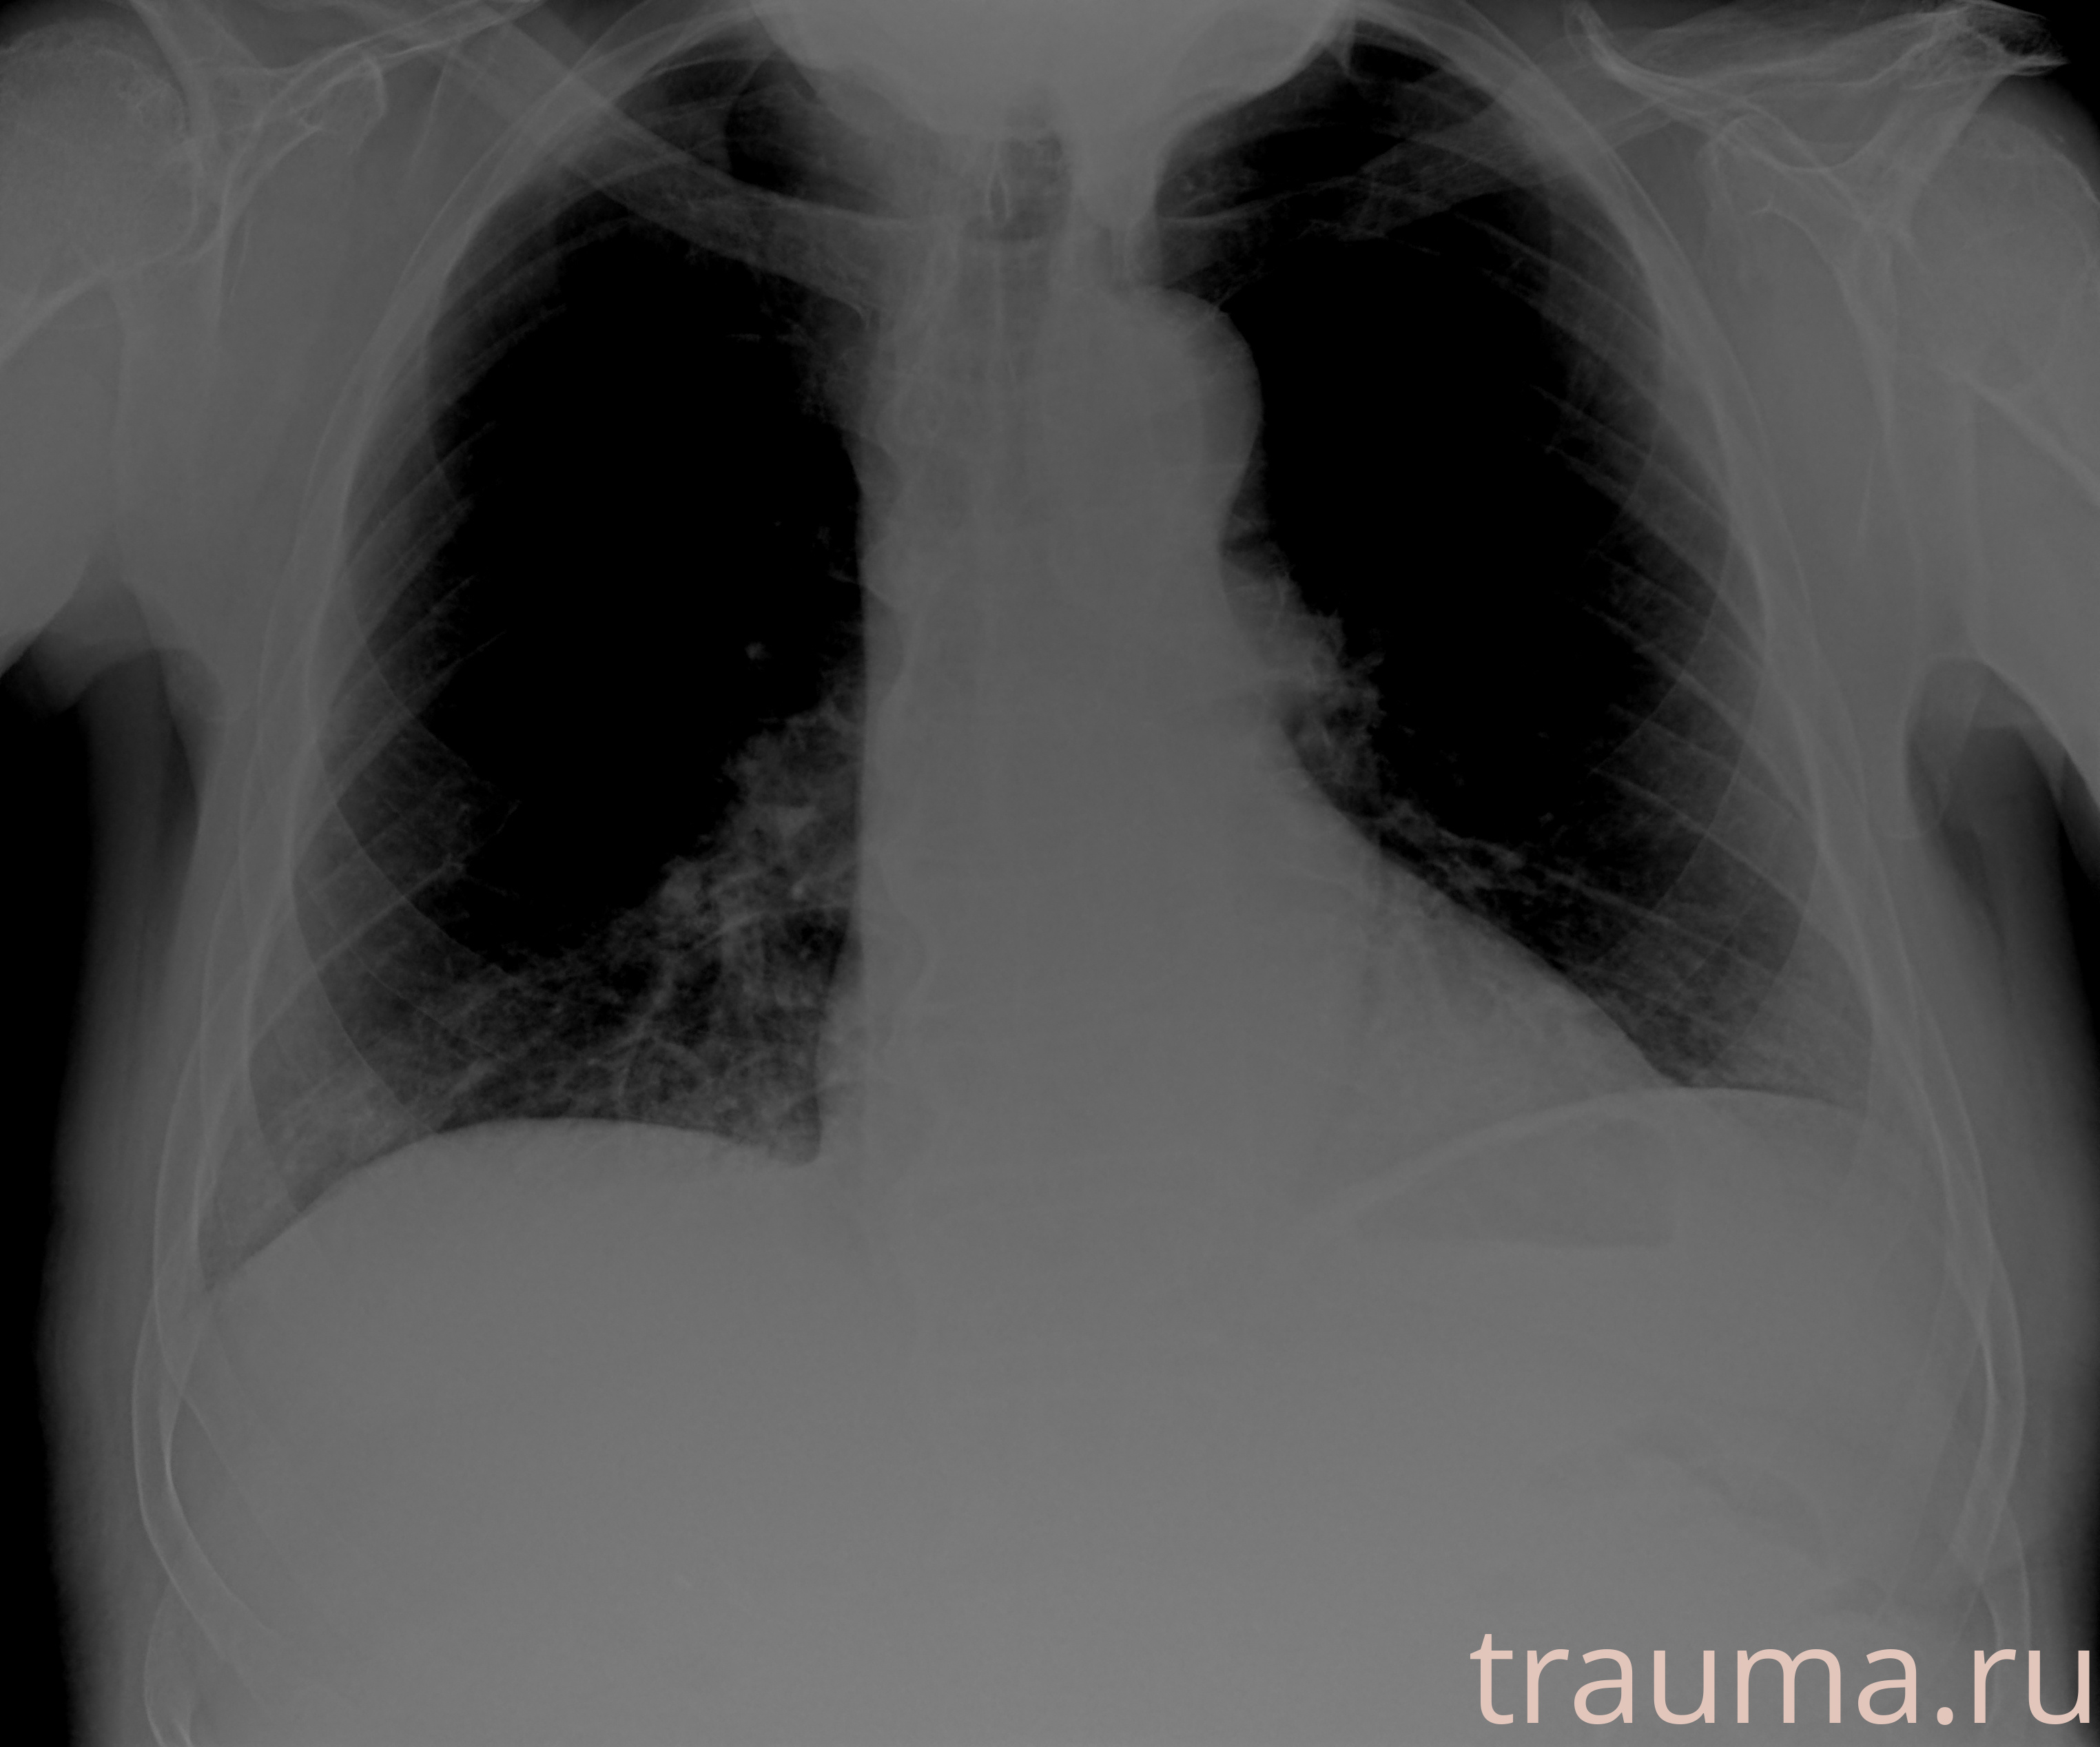

Рентгенограммы

Рентген на дому: по вашему адресу приезжает врач-рентгенолог, травматолог-ортопед с мобильным рентгеновским аппаратом, проводит диагностику травмы или заболевания, делает необходимые рентгенограммы, дает рекомендации по дальнейшему лечению. Получить качественные снимки в домашних условиях возможно благодаря уникальной методике, разработанной МосРентген Центром для института  Склифосовского

при переломе шейки бедра и пневмонии от компании МосРентген Центр - партнера Института имени Склифосовского